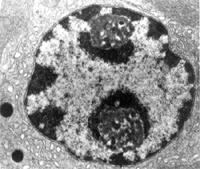

細胞適應症

扁桃體其主要代謝產物是具有大環內酯類活性作用的14—羥基克拉黴素。單劑給藥後血消除半衰期(t1/2()為4.4小時;每12小時口服250mg後的原形藥物血消除半衰期(t1/2()為3~4小時,其代謝物為5~6小時;每12小時口服500mg後的原形藥物的血消除半衰期(t1/2()為5~7小時,其代謝物為6.9~8.7小時。經口服或靜脈注入14C標記的克拉黴素,5日內自尿排出占劑量的36%,自大便排出占52%。低劑量給藥經糞、尿兩個途徑排出的藥量相仿,但劑量增大時尿中排出量較多。

染色體其主要代謝產物是具有大環內酯類活性作用的14—羥基克拉黴素。單劑給藥後血消除半衰期(t1/2()為4.4小時;每12小時口服250mg後的原形藥物血消除半衰期(t1/2()為3~4小時,其代謝物為5~6小時;每12小時口服500mg後的原形藥物的血消除半衰期(t1/2()為5~7小時,其代謝物為6.9~8.7小時。經口服或靜脈注入14C標記的克拉黴素,5日內自尿排出占劑量的36%,自大便排出占52%。低劑量給藥經糞、尿兩個途徑排出的藥量相仿,但劑量增大時尿中排出量較多。